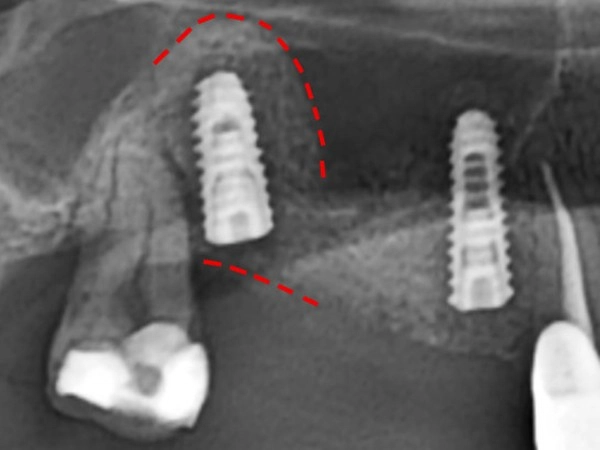

治療前

由於鼻竇空間過大或上顎骨頭萎縮,導致骨頭高度不足